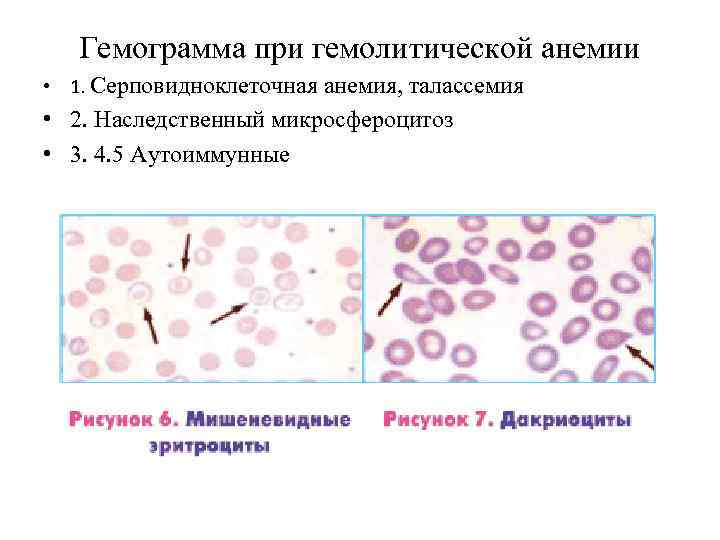

Гемограмма при гемолитической анемии 1. 1 1. 2 5 3 4

Гемограмма при гемолитической анемии • 1. Серповидноклеточная анемия, талассемия • 2. Наследственный микросфероцитоз • 3. 4. 5 Аутоиммунные

Описание гемограммы при гемолитической анемии В гемограмме имеется: 1. Микросфероцитоз 2. Гипохромия 3. Мешеневидный эритроциты 4. Серповидноклеточные эритроциты